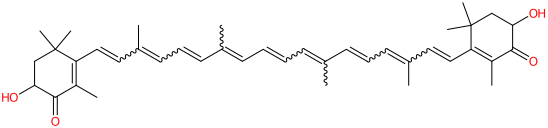

L'astaxantina è un pigmento rosso, cheto-carotenoide naturale liposolubile (appartiene a un gruppo di carotenoidi chiamati xantofille, che includono zeaxantina, beta-criptoxantina, licopene, beta-carotene), un composto chimico sintetico di xantofilla, carotenone costituito da beta,beta-carotene-4,4'-dione. Si trova nell'ambiente marino, biosintetizzata dalla microalga verde Haematococcus pluvialis, dal lievito rosso Phaffia rhodozyma, dai sottoprodotti di crostacei e da fitoplancton. E' stata scoperta per la prima volta nell'aragosta e si accumula in zooplancton, pesci, crostacei. Può anche essere estratta da salmone, trote, orate, krill, gamberetti, varie alghe. Oggi, a causa della grande richiesta, la maggior parte dell'astaxantina è prodotta chimicamente dal chetoisophorone ricavato dal petrolio, mentre solo una piccola quantità viene estratta dalle alghe o lievito.

- Formula molecolare C40H52O4

- Peso molecolare 596.8

- Massa esatta 596.386536

- CAS 472-61-7

- IUPAC (6S)-6-hydroxy-3-[(1E,3E,5E,7E,9E,11E,13E,15E,17E)-18-[(4S)-4-hydroxy-2,6,6-trimethyl-3-oxocyclohexen-1-yl]-3,7,12,16-tetramethyloctadeca-1,3,5,7,9,11,13,15,17-nonaenyl]-2,4,4-trimethylcyclohex-2-en-1-one

- SMILES CC1=C(C(CC(C1=O)O)(C)C)C=CC(=CC=CC(=CC=CC=C(C)C=CC=C(C)C=CC2=C(C(=O)C(CC2(C)C)O)C)C)C